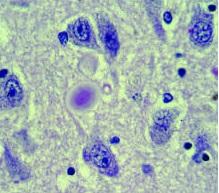

PARKINSON: L'hypothèse d'une maladie auto-immune?